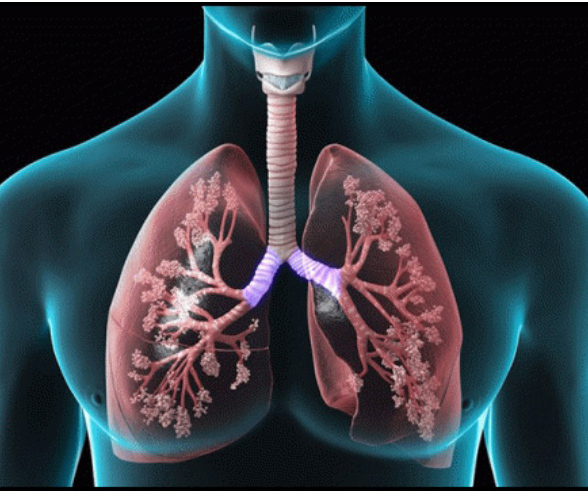

COPD

Chronic Bronchitis

Emphysema

Homeopathy Treatments for SINUS

How Homeopathy Can Cure Your Sinusitis

Homeopathy offers a tailored approach for sinusitis relief by addressing individual symptom patterns and aiming to stimulate the body’s natural healing mechanisms. Multiple clinical and observational studies highlight significant improvement in both acute and chronic sinusitis following homeopathic treatment In a controlled randomized double-blind trial, about 81% of acute sinusitis patients and 67% of chronic sinusitis patients recovered a recovery rate comparable to conventional treatments like antibiotics and decongestants. Large-scale, multi-centric research involving hundreds of patients has shown that homeopathic remedies selected on the basis of the patient’s specific pathology and symptoms led to statistically significant reduction in sinusitis symptoms and improved radiological findings over periods of three to six months. Medications such as Silicea, Calcarea carbonica, Lycopodium, Phosphorus and Kali iodatum were among the most effective providing marked improvement for many Furthermore long-term follow-up studies reveal that improvements with homeopathy can persist for several years leading to sustained reductions in symptom severity and enhancement in quality of life without notable complications. While homeopathic management of sinusitis has demonstrated high success rates and safety further controlled trials are necessary to confirm its efficacy as an alternative or complementary option to standard medical therapy.

Homeopathy Treatments for SINUS

Why Choose Homeopathy for SINUS?

Choosing homeopathy for sinus problems offers a natural, individualized approach that aims not only to relieve symptoms but also to address the root causes of sinusitis. Homeopathic remedies are derived from plants and minerals and work by stimulating the body’s own immune system, helping to clear sinus congestion reduce infections and prevent recurrences unlike conventional treatments that may simply suppress symptoms or carry risks of side effects such as fungal infections. Large-scale studies have shown that people with chronic sinus issues achieved significant lasting improvements in symptoms and quality of life after homeopathic treatment, with benefits persisting for years and no major complications reported. Homeopathy is also considered safe and non-invasive, making it a preferred option for many who wish to avoid repeated courses of antibiotics or surgery. Additionally, homeopathy offers personalized treatment options with remedies tailored to the specific symptoms and needs of each patient, making it a holistic solution for sinus health.

How Homeopathy Boosts Immunity Against Sinus Infections

Homeopathy offers a unique holistic approach to managing sinus infections by not just alleviating symptoms but actively working to strengthen the body’s immune defenses and prevent recurrences Unlike conventional treatments that merely suppress symptoms or rely on medication with potential side effects homeopathic remedies are designed to mimic sinusitis symptoms in highly diluted forms stimulating the body’s natural healing responses and encouraging the production of antibodies.

When to Choose Homeopathy for Sinusitis

Homeopathy can be considered for sinusitis when you are seeking a safe, individualized and long-term solution especially if conventional treatments have provided only temporary relief or caused unwanted side effects. It is particularly suitable for those experiencing chronic sinusitis—persistent symptoms such as blocked nose, facial pain and headaches that don't resolve despite standard care or for individuals prone to recurrent sinus infections. Homeopathic remedies work by addressing the root causes of sinus inflammation such as underlying allergies, immune imbalances, or sensitivities, rather than just suppressing symptoms. They are tailored to each person’s unique symptom profile and overall constitution making the approach highly personalized. The effectiveness of homeopathic treatment for sinusitis is supported by observational studies showing significant and sustained improvements in complaint severity and quality of life lasting for years in chronic cases. Additionally, homeopathy is gentle safe for all ages and free from side effects making it a valuable option for patients looking for holistic non-invasive relief or wishing to prevent recurrences without long-term medication dependence. Professional consultation is advised for chronic or complicated cases to ensure a remedy is well matched to your symptoms and health history.